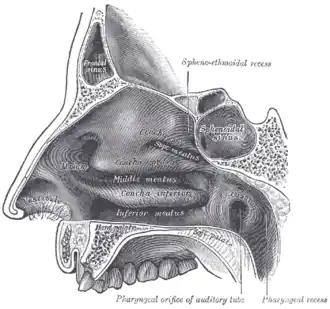

Sagittalschnitt Blick nach seitlich (lateral) auf die Seitenwand (in Richtung auf die Kieferhöhle)

Sagittalschnitt Blick nach seitlich (lateral) auf die Seitenwand (in Richtung auf die Kieferhöhle) -

Als Recessus sphenoethmoidalis oder Recessus sphenoethmoideus bezeichnet man die Vertiefung zwischen dem Keilbeinkörper und der oberen Nasenmuschel, in welche mit enger Schleimhautöffnung die Keilbeinhöhle einmündet. Ein Recessus ist eine Vertiefung, Ausbuchtung oder Tasche.

Siehe auch nebenstehende Abbildung von Henry Vandyke Carter. Wegen der Spiegelung erkennt man in der rechten Bildhälfte die drei rechten Conchae mit ihren vier Meatus und spiegelsymmetrisch in der linken Bildhälfte die drei linken Conchae mit ihren vier Meatus.